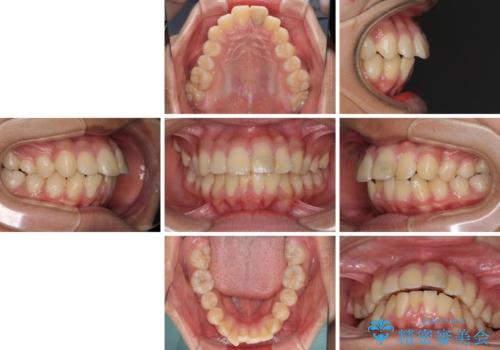

膨らんだ口元 ワイヤー装置での抜歯矯正

- 口元の突出感を気にして来院された患者様です。

上下前歯が著しく前突している状態であったので、上下左右の第1小臼歯4本を抜歯し、ワイヤー装置にて矯正治療を行うこととしました。

舌の突出癖により、前突になったと考えられたため、舌のトレーニングをしっかりと行うよう指導しました。